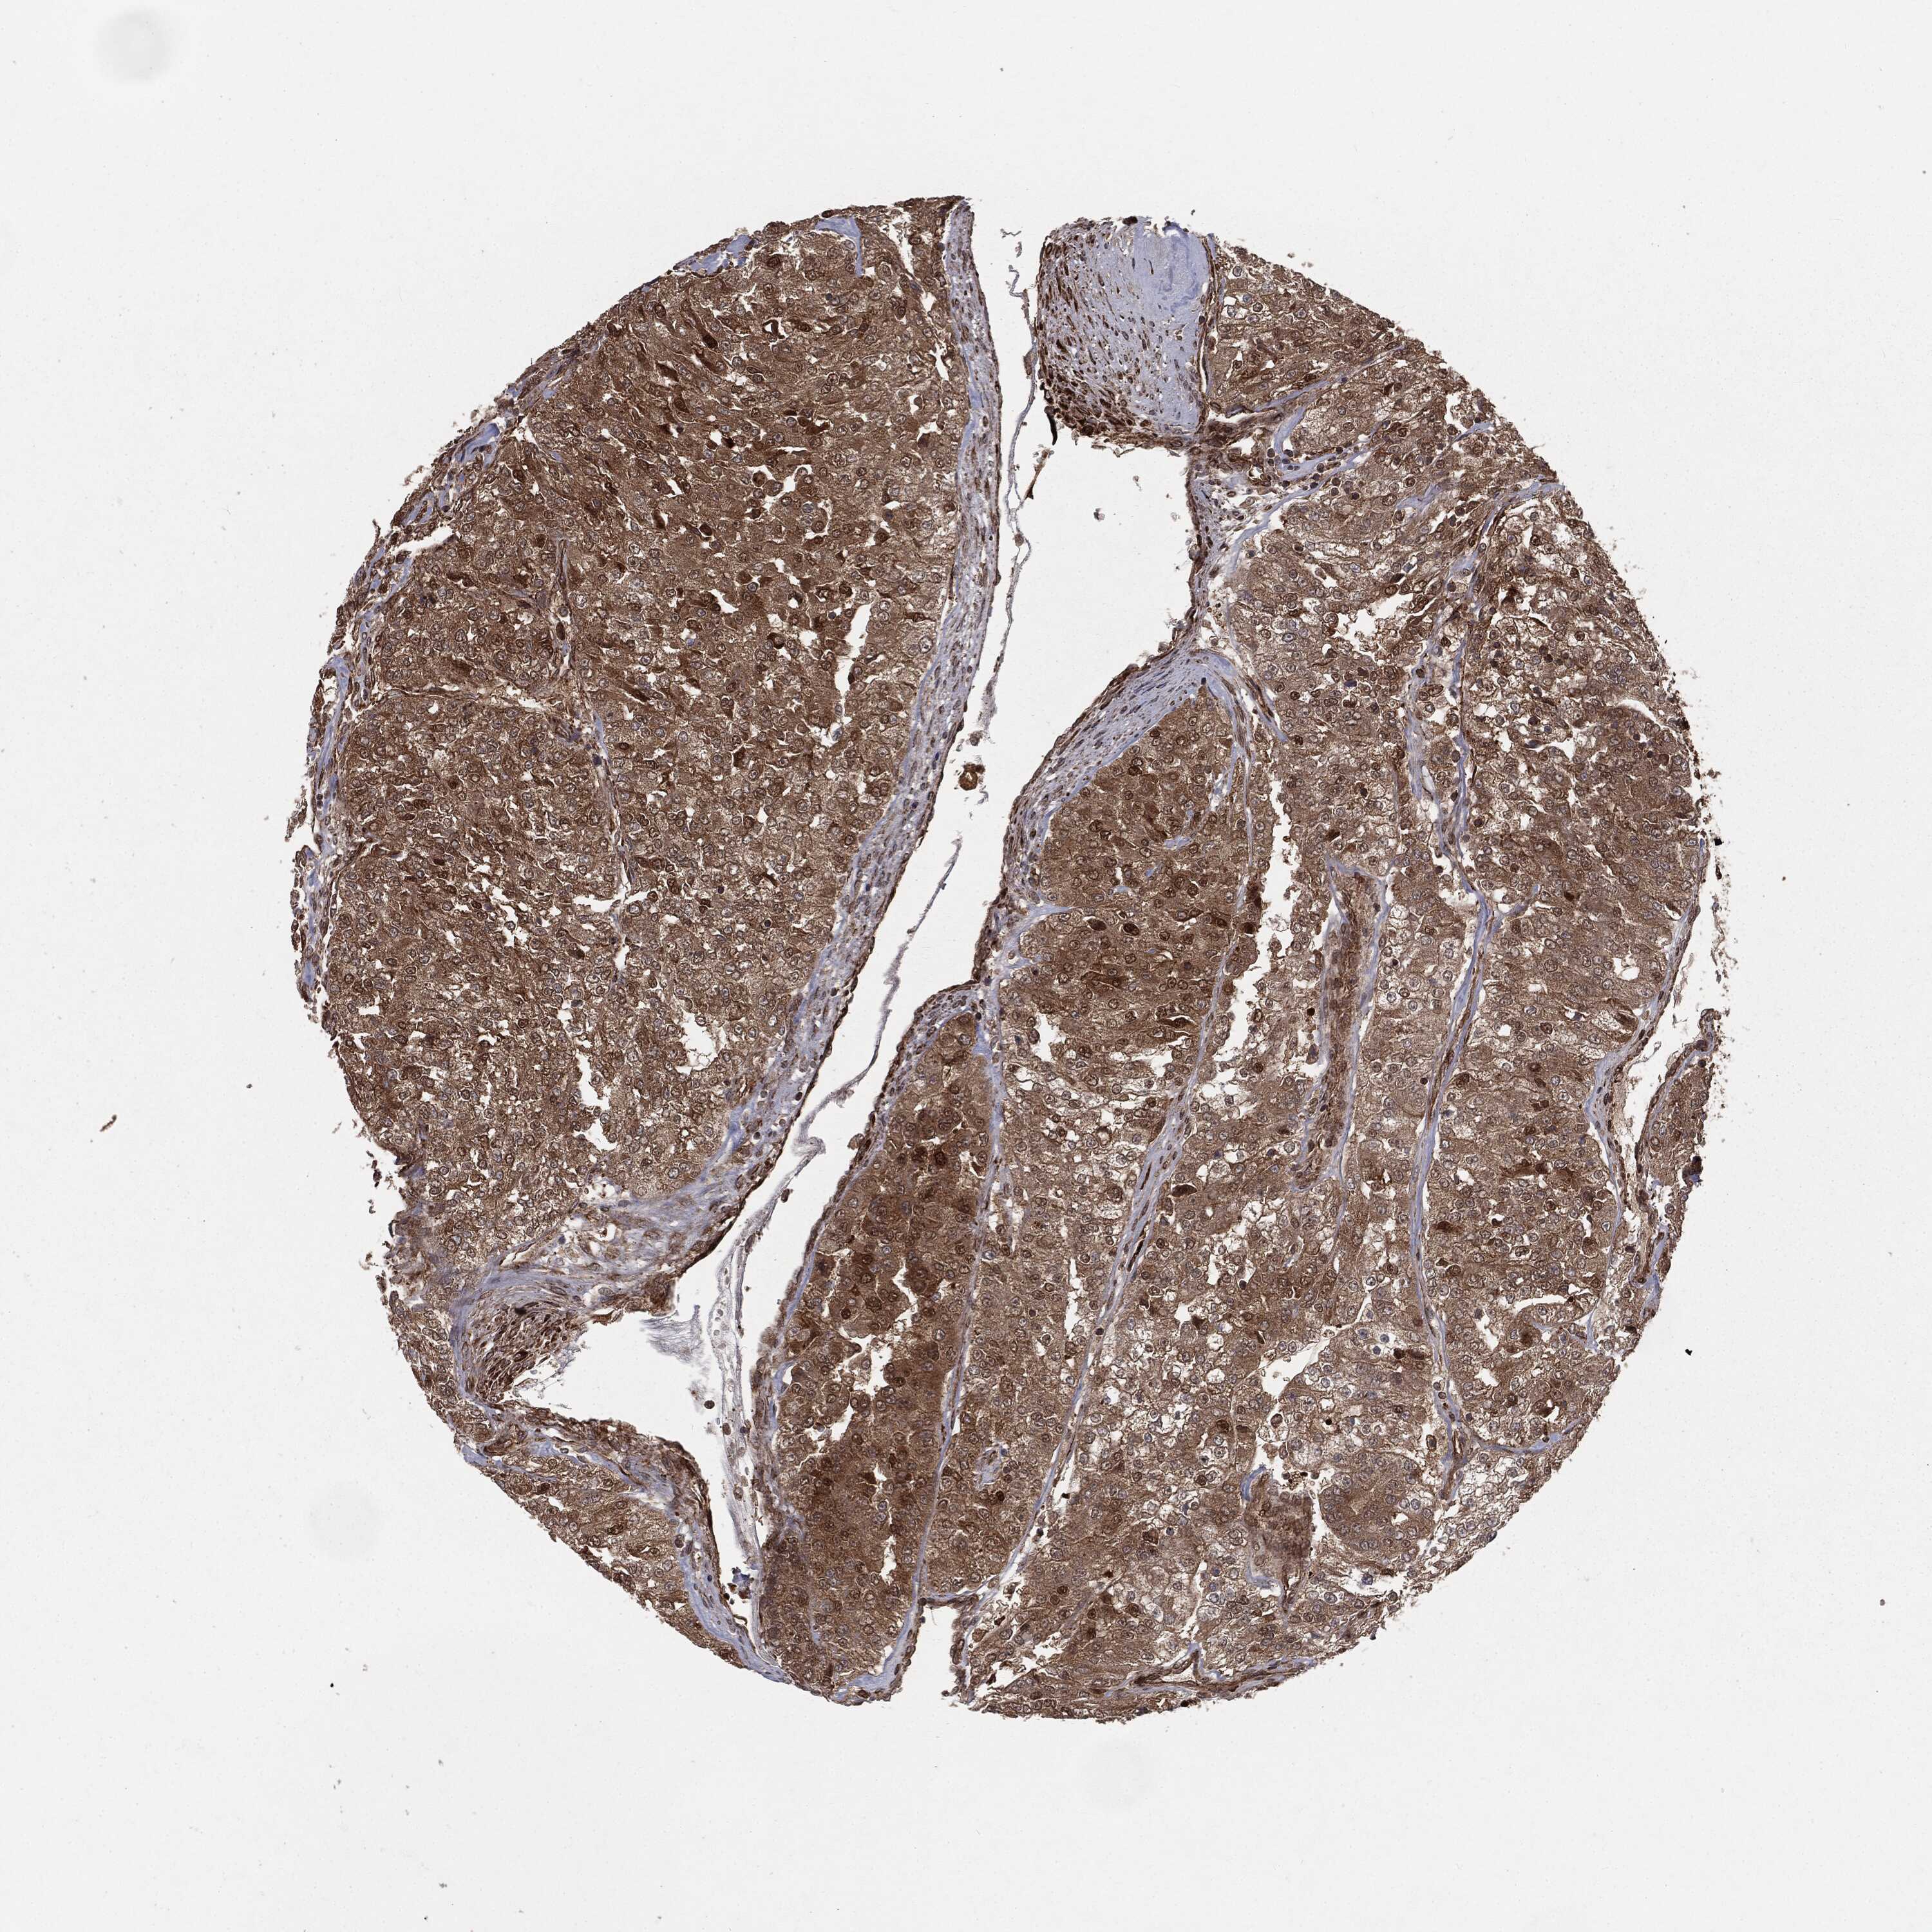

KIDNEY RENAL CLEAR CELL CARCINOMA (VALIDATION) - Interactive survival scatter ploti

The Survival Scatter plot shows the clinical status (i.e. dead or alive) for all individuals in the patient cohort, based on the same data that underlies the corresponding Kaplan-Meier plots. Patients that are alive at last time for follow-up are shown in blue and patients who have died during the study are shown in red.

The x-axis shows the expression levels (FPKM) of the investigated gene in the tumor tissue at the time of diagnosis. The y-axis shows the follow-up time after diagnosis (years). Both axes are complimented with kernel density curves demonstrating the data density over the axes. The top density plot shows the expression levels (FPKM) distribution among dead (red) and alive patients (blue). The right density plot shows the data density of the survived years of dead patients with high and low expression levels respectively, stratified using the cutoff indicated by the vertical dashed line through the Survival Scatter plot. This cutoff is automatically defined based on the FPKM cutoff that minimizes the p-score. The cutoff can be changed by dragging the vertical line or by entering a cutoff value in the square labeled "Current cut-off".

Under the Survival Scatter plot the p-score landscape (black curve; left axis) is shown together with dead median separation (red curve; right axis). Dead median separation is the difference in median mRNA expression between patients who have died with high and low expression, respectively. It is calculated as follows: median FPKM expression of dead patients with high expression - median FPKM expression of dead patients with low expression. This is intended to aid the user in visually exploring custom cutoffs and the associated p-scores and dead median separation.

Individual patient data is displayed and can be filtered by clicking on one or more of the category buttons on the top of the page. Categories describing expression level and patient information include: high, low, alive, dead, female, male and tumor stages. The scale of the x-axis can be toggled between linear and log-scale by clicking on the "x log" button. Mouse-over function shows TCGA ID, patient information and mRNA expression (FPKM) for each patient.

& Survival analysisi

Kaplan-Meier plots summarize results from analysis of correlation between mRNA expression level and patient survival. Patients were divided based on level of expression into one of the two groups "low" (under cut off) or "high" (over cut off). X-axis shows time for survival (years) and y-axis shows the probability of survival, where 1.0 corresponds to 100 percent.

RANBP9 is not prognostic in Kidney Renal Clear Cell Carcinoma (validation)

Best expression cut offi

Based on the FPKM value of each gene, patients were classified into two groups and association between prognosis (survival) and gene expression (FPKM) was examined. The best expression cut-off refers the FPKM value that yields maximal difference with regard to survival between the two groups at the lowest log-rank P-value. Best expression cut-off was selected based on survival analysis .

When clicking on this number, the vertical dashed line indicating cut-off, the interactive survival plot, and the Kaplan-Meier curve will be adjusted to show results based on the best expression cut-off.

: 15.72

TCGA RNA samplesi

RNA-seq data is reported as average FPKM (number Fragments Per Kilobase of exon per Million reads), generated by the The Cancer Genome Atlas (TCGA) .

Normal distribution across the dataset is visualized with box plots, shown as median and 25th and 75th percentiles. Points are displayed as outliers if they are above or below 1.5 times the interquartile range. FPKM values of the individual samples are presented next to the box plot.

Average pTPM 20.5

Number of samples 100